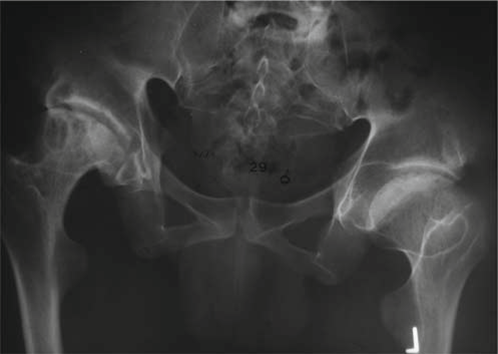

Initial Radiographs (Bilateral Hips with pelvis AP and frog-leg lateral views):

The initial radiographic series provided critical insights into the extent of the patient's skeletal dysplasia and secondary degenerative changes.

* Key Findings:

* Severe bilateral coxa magna and coxa plana: The femoral heads were significantly enlarged in overall diameter but profoundly flattened, demonstrating irregular ossification. The femoral necks appeared short and broad.

* Acetabular Dysplasia: Both acetabula exhibited shallow morphology, consistent with dysplasia. Sclerotic changes and subchondral cyst formation were evident in the weight-bearing areas.

* Joint Space Narrowing: There was complete obliteration of the superior and anterior joint spaces bilaterally, indicative of severe osteoarthritis.

* Osteophytes: Extensive peripheral osteophyte formation was observed circumferentially around both femoral heads and acetabular margins.

* Subchondral Sclerosis: Diffuse subchondral sclerosis was apparent, reflecting the chronic degenerative process.

* Overall Impression: These features were pathognomonic for severe secondary osteoarthritis resulting from chronic epiphyseal dysplasia.

* This image displays an anteroposterior radiograph of the pelvis, illustrating the characteristic findings of advanced bilateral hip osteoarthritis in the setting of Multiple Epiphyseal Dysplasia, specifically exhibiting irregular and flattened femoral heads (coxa plana) and broadened femoral necks (coxa magna), coupled with severe joint space narrowing and acetabular remodeling.